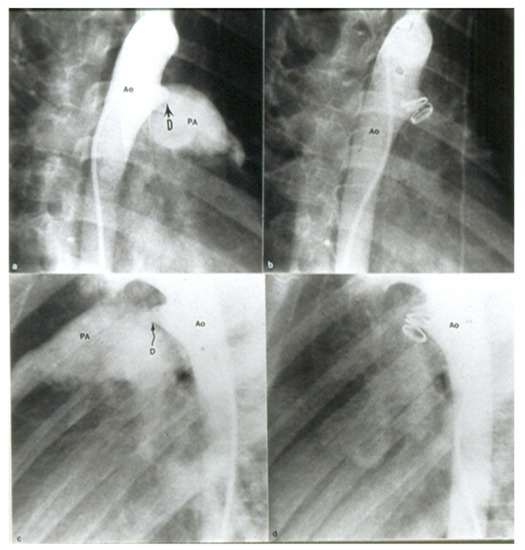

HOT ! 健康・医学 Surgery for congenital heart defects Surgery for Congenital Heart Defects: Stark, J., De Leval, M

健康・医学 Surgery for congenital heart defects Surgery for Congenital Heart Defects: Stark, J., De Leval, Mの詳細情報

Surgery for Congenital Heart Defects: Stark, J., De Leval, M。41p23CSocqL.jpg_BO30,255,255,。Young Woman Undergoes First-Of-Its-Kind Surgery for Rare。医学書 先天性心疾患手術書この道では、いい本だったようですが絶版なのかもしれません。Care and Treatment for Congenital Heart Defects | American。アマゾンで調べると、同タイトル、同執筆者の本がありますが、第3版とあるのですが、同じ系列なのかはわかりません。【裁断済】プロメテウス解剖学コアアトラス = PROMETHEUS Atlas。因みに、その本は専門書ですので500ユーロ以上、日本円では4万円程のようです。ハーブ美容法: インド三千年の秘伝 - シャナーズ・フセイン。1610g18.5x26.6x4

• Surgery for Congenital Heart Defects: Stark, J., De Leval, M